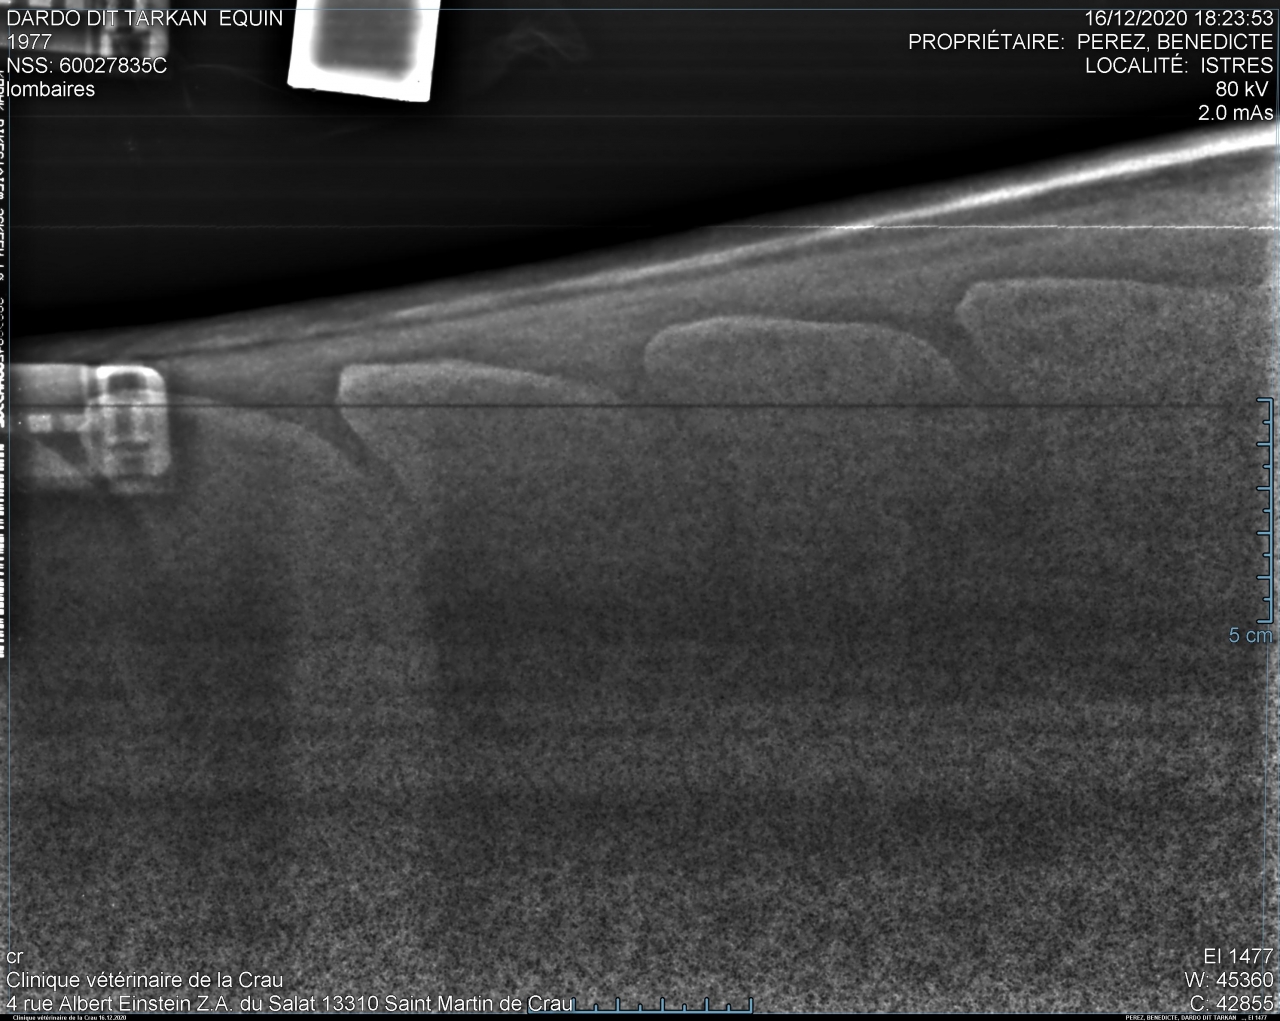

| Dire merci1 | allez pcq je suis sympa en spoiler pour pas polluer et pcq il y a mon nom de famille aussi ![]() |

| Dire merci | Ah ouais punaise lui c’est costaud! ![]() La mienne y a des rétrécissements des espaces mais rien ne se touche. |

| Dire merci | Ah oui !! ![]() Du coup..... Dardo dit Tarkan ??? |

Par takhan : le 11/04/24 à 18:29:23

| Dire merci | Dardo oui mais la véto a écrit tarkhan alors que c'est bien takhan ![]() Puis a mon avis depuis ça s'est aggravé. Si je farfouille je devrais pouvoir retrouver celles de 2016 pour voir l'évolution en quelques années. ![]() |